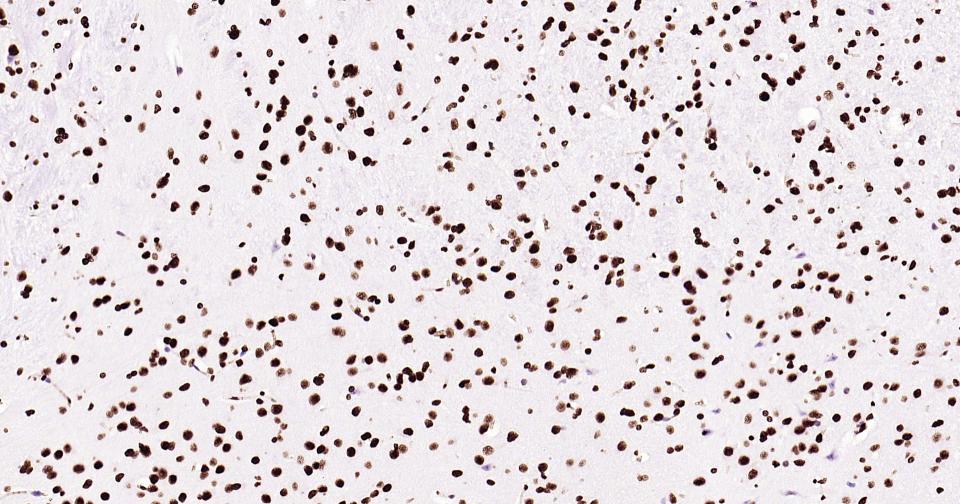

Histone H3 is one of the DNA-binding proteins found in the chromatin of all eukaryotic cells. H3 along with four core histone proteins binds to DNA forming the structure of the nucleosome. Histones play a central role in transcription regulation, DNA repair, DNA replication and chromosomal stability. Post translationally, histones are modified in a variety of ways to either directly change the chromatin structure or allow for the binding of specific transcription factors. The N-terminal tail of histone H3 protrudes from the globular nucleosome core and can undergo several different types of post-translational modification that influence cellular processes. These modifications include the covalent attachment of methyl or acetyl groups to lysine and arginine amino acids and the phosphorylation of serine or threonine.

用吸水纸吸去玻片上多余的液体,加入2-4滴大鼠Histone H3 鼠单抗工作液(试剂5),置于湿盒中,4℃孵育过夜或37℃孵育1-2 h。

*5. 发表论文时引用本产品的写作建议 "IHC0111R, Bioss Antibodies"。引用示例: “Rat tissue sections using Rat Histone H3 IHC Kit (IHC0111R, Bioss Antibodies) were stained for Histone H3 according to the manufacturer's instructions.”